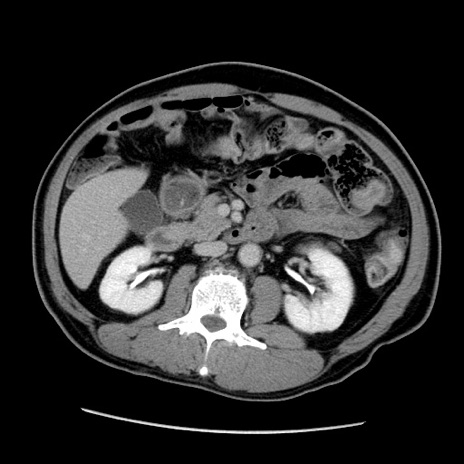

症例22(横断像)

【症例】50歳代男性

【主訴】腹痛

【現病歴】AVMからの被殻出血のため回復期リハ病棟入院中。 本日午後3時頃急に下腹部痛が出現した。

【既往歴】AVM、被殻出血、虫垂炎、高血圧

【身体所見】意識晴明、左半身不全麻痺、会話の理解は良好、36.5°C、腹部:膨隆、全体に板状硬、下腹部正中に圧痛点あり、反跳痛-、筋性防御不明、右下腹部にope scar

【データ】WBC 9400、CRP 0.06